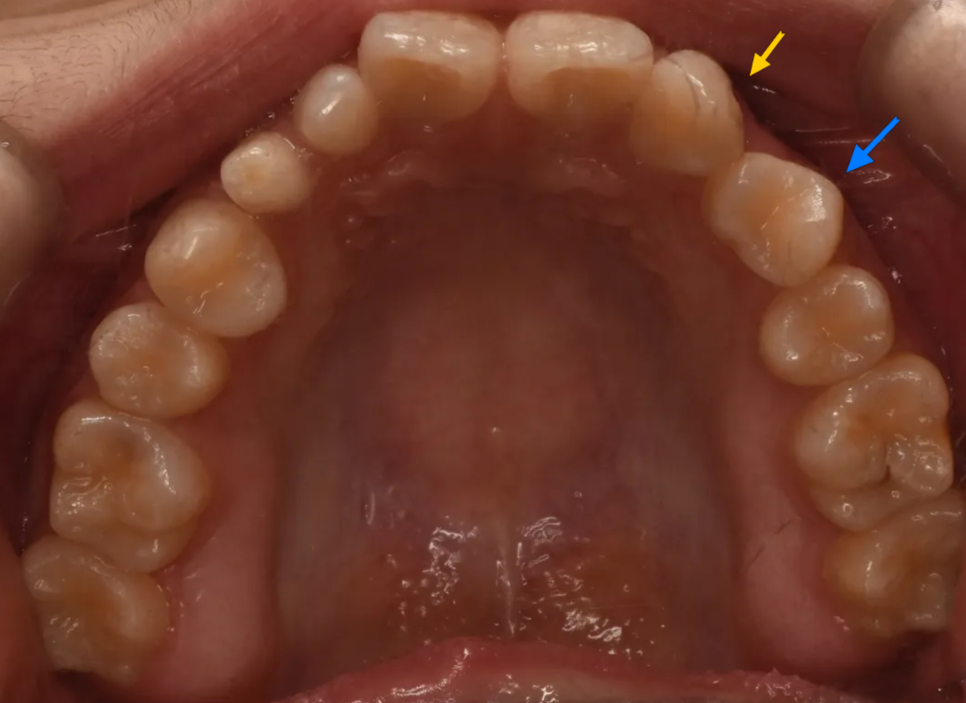

첫번째로 가장 눈에 띄는 것은 사이즈가 유난히 작은 치아들이 존재하는 것입니다. 아래 그림에서 붉은색 화살표는 초등학교때 빠졌어야 할 유치(젖니)가 빠지지 않고 아직 남아있는 경우(유치잔존)입니다. 그래서 다른 치아들(영구치)보다 크기가 작은 것입니다. 노란색 화살표는 선천적으로 이가 작게 태어나는 "왜소치"인 경우입니다.

여기서 젖니가 아직까지 남아있는 이유는, 영구치 송곳니가 매복되어 있어 나오지 못했기 때문입니다. 이는 엑스레이를 찍어보면 깊이 묻혀있는 송곳니를 보면 알 수 있습니다.

다음으로 눈에 띄는 것은 있어야 할 이가 없는 경우(결손치)인 경우입니다. 아래 그림에서 표시된 이는 작은앞니(측절치)위치에 있지만 실제로는 송곳니입니다. 즉 작은앞니가 없는 공간으로 뒤쪽에 있던 송곳니가 밀려나온 경우입니다. 그리고 공간이 남기 때문에 그 뒤의 작은어금니가 공간을 채우면서 회전되어 있는 것이 보입니다.

노랑: 결손된 측절치 위치로 밀려나온 송곳니 / 파랑: 공간을 채우느라 회전한 작은어금니